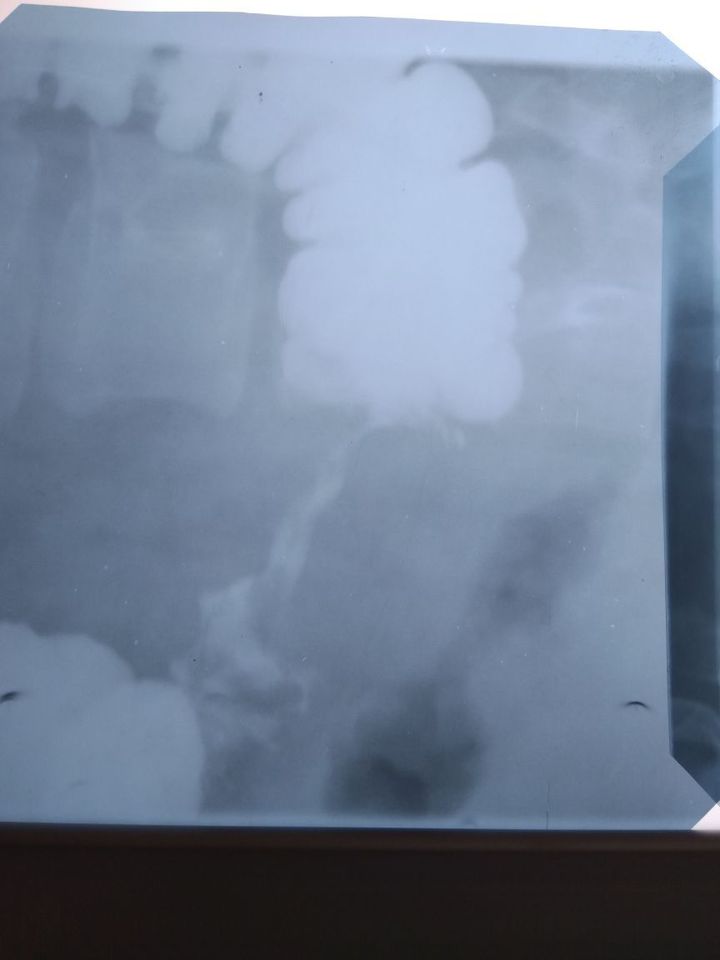

Radiology case

Radiology

Xray

Radiography

Radiograph

Is this an apple core sign?